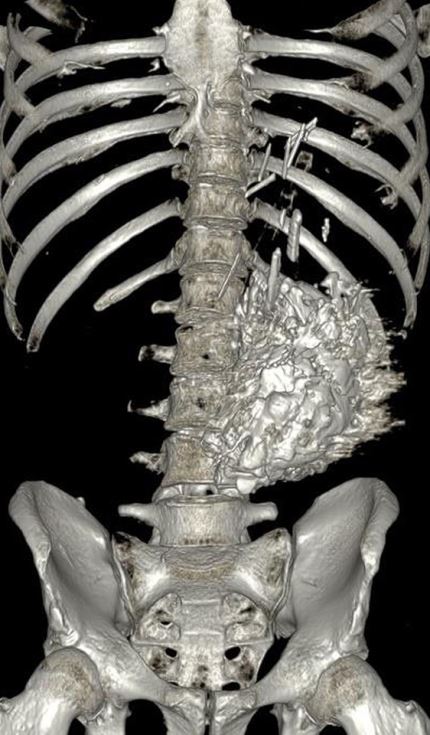

Seit zwei Wochen musste sich ein 42-jähriger Mann regelmäßig erbrechen; zudem hatte er über die letzten drei Monate 10 kg Gewicht verloren. Er wurde schließlich in einer internistischen Klinik vorstellig. Der Mann litt an einer schweren chronischen Schizophrenie, nahm aber keine Medikamente ein.

CT und 3D-CT-Rekonstruktion einer Raumforderung im Magen.

© CMAJ. 2024;196:E906-7